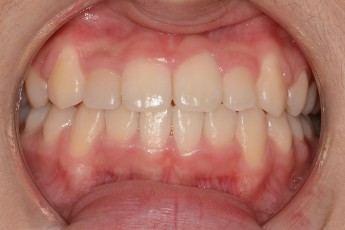

Before

After